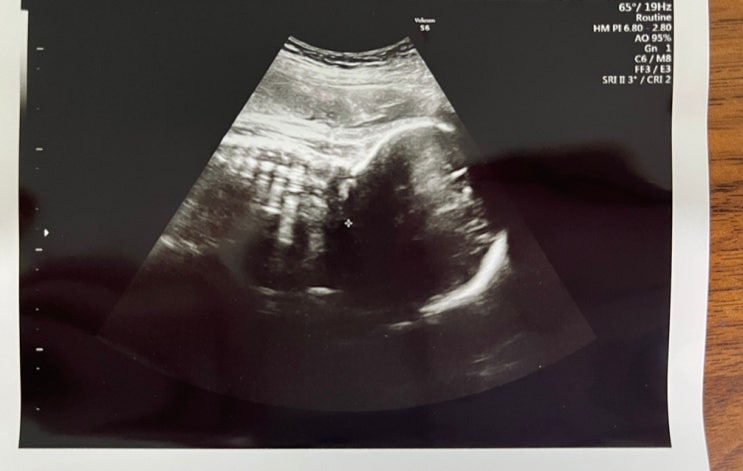

3월 27일 수요일, 39주 3일차 검진 몸은 너무나도 가볍고.. 오구는 나올기미가 안보임 오늘도 역시나 검진...

3월 21일 목요일, 38주 3일차 검진 아직 오구 나올 기미 안보임.. 그리고 1주일사이에 또 많이 커버린 우리...